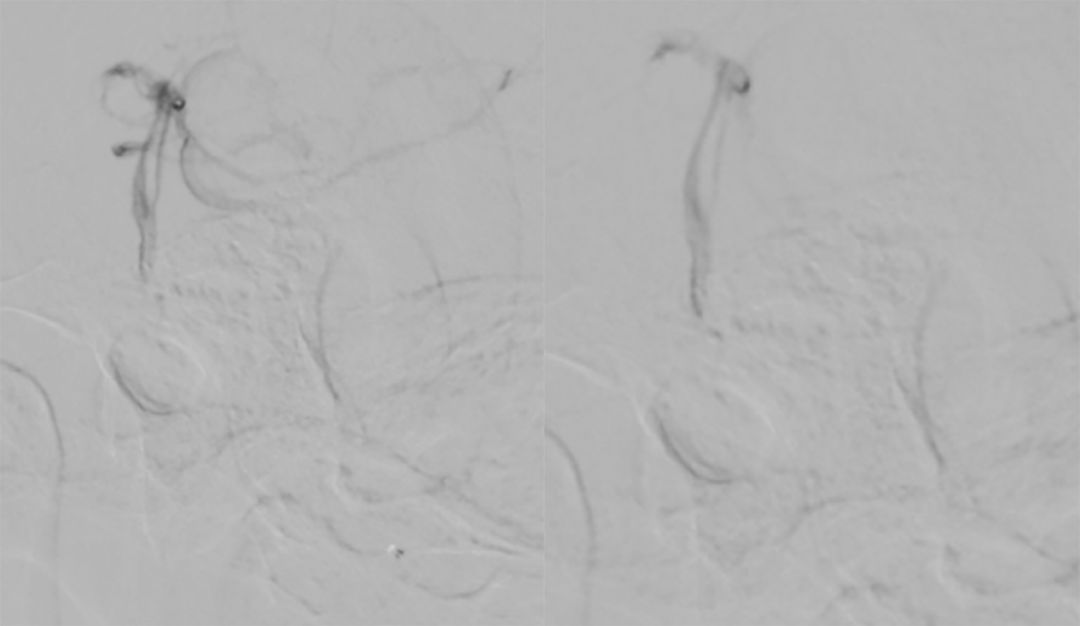

4. 最后将Echelon-10微导管置入基底动脉中下段进行微量造影:基底动脉2个管腔、 双侧大脑后动脉显影、小脑上动脉均可显影(图8)。

图8

基底动脉进行三维血管重建:基底动脉有较粗和较细的2个管腔,左侧小脑上动脉瘤大小约2.3*2.1 mm(图9)。

图9

进行上述三次微量造影均可见双侧大脑后动脉显影,以及结合基底动脉三维重建图像,故判断基底动脉属于开窗,而非夹层。由于载瘤动脉较细,拟行单微管动脉瘤栓塞术。